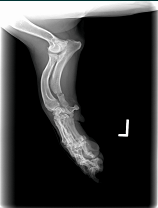

Hey Bob,Sorry, Ive been in and out of town.  I've attached some radiographs of a 12 year-old dog with an ulnar fracture we've been using it on.  It looks like we have significant callous formation in 16 days!  I have another dog that I did a patellar luxation surgery that we are using it on as well.  I'll try to get you some films of it.  So far I haven't had any major issues.  It would be nice if the device itself could be smaller for some of these smaller dogs.  The fracture dog has a bandage/splint on, so it is pretty easy to encorporate the coils into the bandage.  The other dog has no bandage, so I've been using elasitcon to hold it over the affected area.  After a 4-5 days it causes some irritation and we have the device off a couple of days before replacing it.  I'm not sure there is any other way to hold it there(over the knee) without putting a bandage over the leg which would limit our range of motion and cause muscle atrophy.Thanks,

Ian Voeizel, DVM